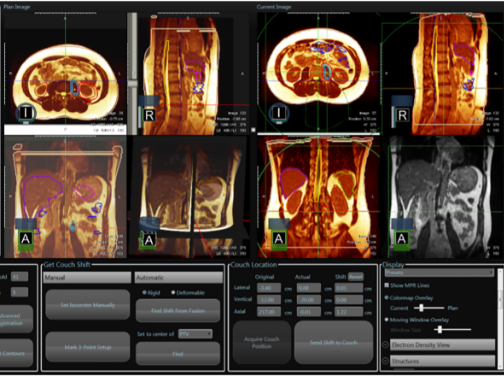

当院のMRIガイドIGRT治療器、MRIdian(ViewRay社製)は国立がん研究センター中央病院以降、国内では2台目、平成30年9月から当院で稼働しています。MRIdianの最も優れた特徴はMRI連速撮影によるリアルトラッキングです。(動体追跡照射法:迎撃法)。 図1の赤いターゲットの中に治療部位が納まった時だけ、自動的に照射がOnになり、ターゲットの枠から外れると自動的に照射がOffになります。 この技術により、肺がんや肝がんなど、動きが大きい腫瘍にもタイミングを合わせて照射することで、正常臓器への余分な被ばくを減らすことが可能になりました。

図1.治療中、連続撮影のシネ画像(赤色:ターゲット枠、青色:治療部位)

図2.MRIが追うによる位置照合